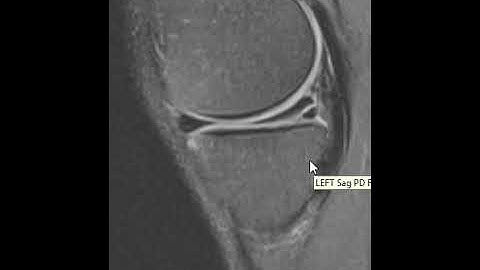

How to read a knee MRI?